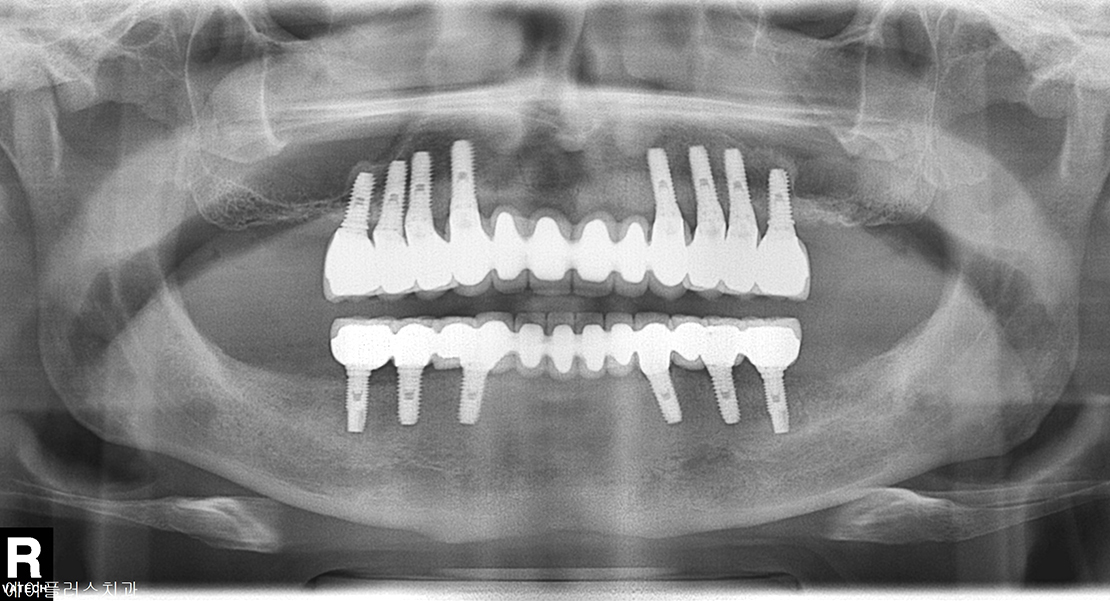

Implant Placed

Restorations

Completed